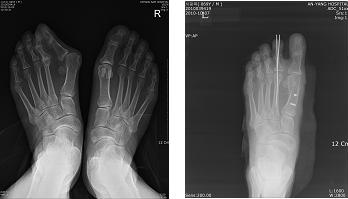

무지외반증 치료 전후 사진

증상이 경미할 경우에는 볼이 넓고 편안한 신발을 착용하여 통증을 줄일 수 있으나, 신발을 신기 어려울 정도로 변형이 심하게 일어났다면 수술로 교정하는 방법이 있다.

과거에는 튀어나온 뼈만 깎는 수술을 시행하여 재발이 많았지만 최근에는 수술기법이 발달하면서 뼈를 깎는 수술 이외에 뼈의 정렬을 바로 잡아주는 작업(절골술, 골유합 등)을 같이 시행해서 재발률이 현격히 낮아졌다. 수술은 입원 없이 발만 마취하여 시행할 수 있으며 수술 후 3일 정도면 보호 신발을 신고 일상생활로 복귀할 수 있다.